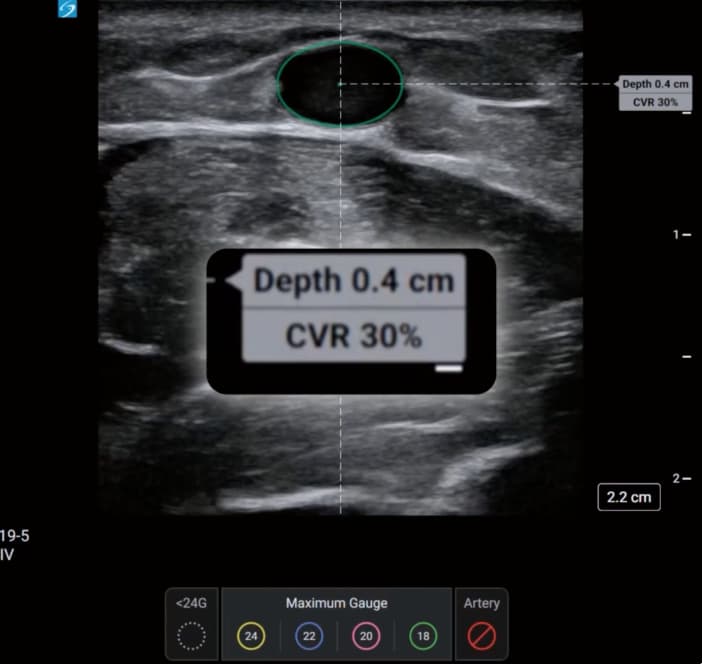

The AI-driven tool aims to assist healthcare professionals by identifying candidate veins and assessing vessel size during pre-procedural scanning. PIV Assist provides real-time differentiation between veins and arteries whilst calculating the catheter-to-vein ratio (CVR) to recommend maximum cannula sizes.

The system employs colour-coded visual guidance to assist procedural planning. Veins are marked according to maximum recommended catheter gauge, whilst arteries appear highlighted in red. The feature displays CVR calculations in real-time and indicates the depth to the centre of each identified vessel.